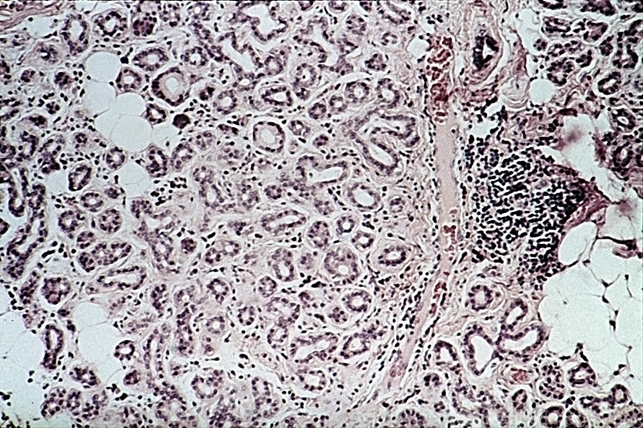

- lacrimal gland, glandular tissue

- Ectopic lacrimal gland. Rather normal-appearing glandular tissue shows focus of inflammation on left side (H&E x lOl).